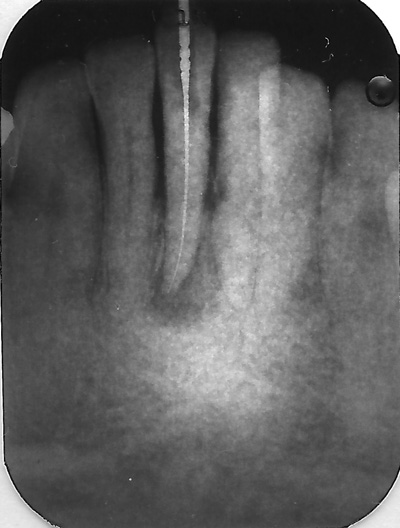

- Under behandlingen